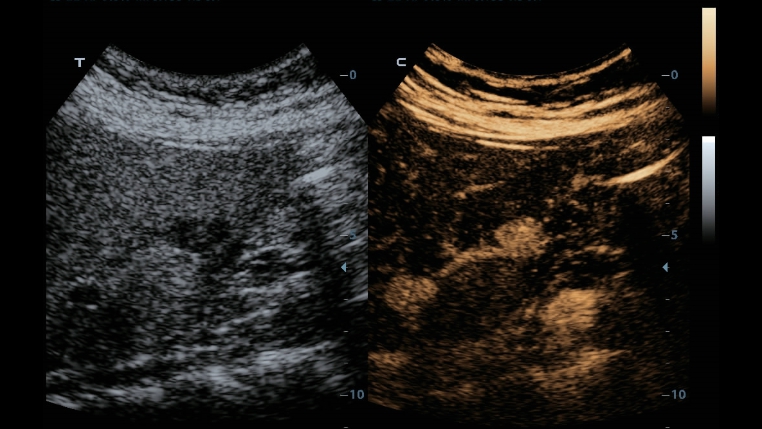

Tecnologie di imaging classiche: migliorare la qualitĂ a scopo diagnostico

Con l'applicazione delle tecnologie di imaging tradizionali, migrate da sistemi a ultrasuoni consolidati, DC-40 con Full HD offre immagini di qualitĂ estremamente dettagliate.

- iClear (tecnologia di imaging con riduzione del rumore)

- PSH(Phase Shift Harmonic Imaging)

- iBeam: ?tecnologia di imaging spaziale âCompoundâ